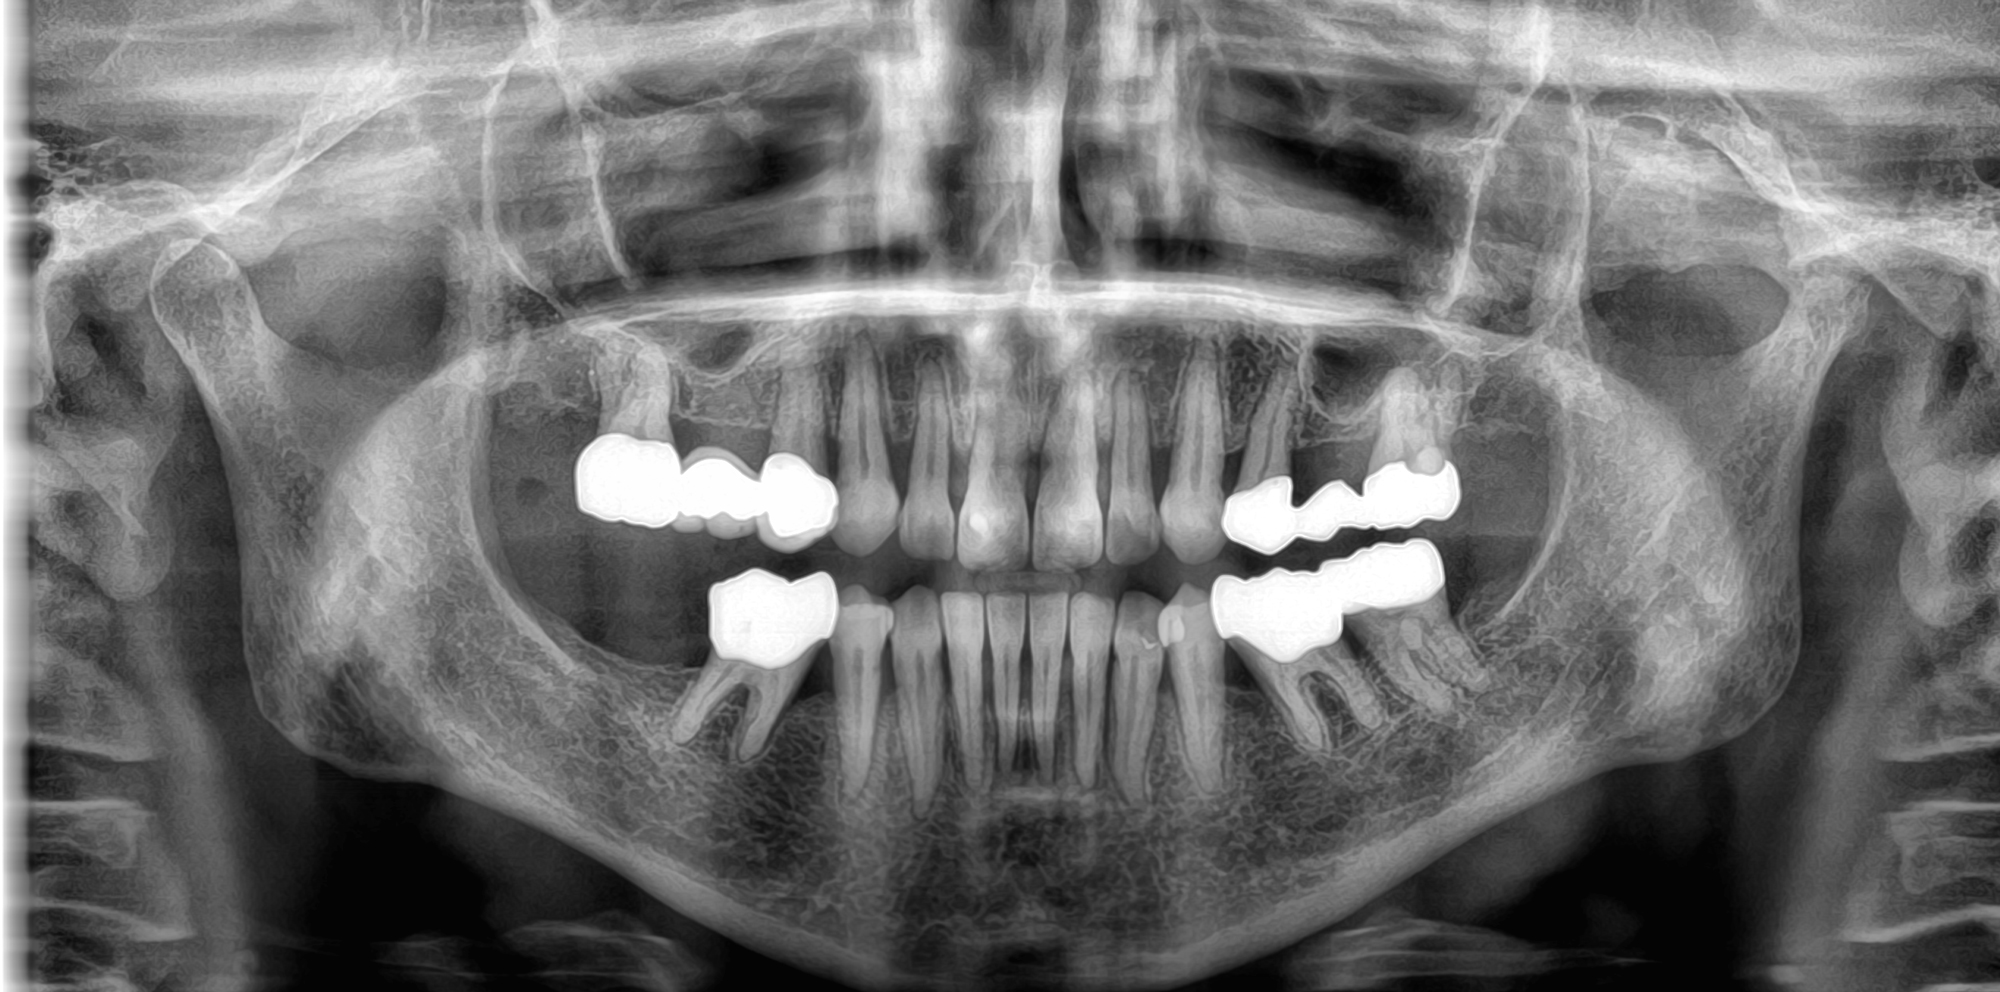

Το νέο μοντέλο CS 8200 3D Neo Edition της Carestream Dental συνδυάζει Ψηφιακή Πανοραμική με Ογκομετρικό Τομογράφο CBCT, με επιλογή εννέα οπτικών πεδίων και ανάλυση έως 75μm.

Με νέο εύχρηστο λογισμικό και ακόμα μεγαλύτερες δυνατότητες όπως το CS MAR, αλγόριθμος NAR, ανατομικά φίλτρα Endo, Perio,τεχνολογία Tomosharp, το καθιστούν ως το πιο κατάλληλο μηχάνημα για Οδοντιατρεία και Διαγνωστικά κέντρα καλύπτοντας όλο το φάσμα των απεικονίσεως οδοντογναθοπροσωπικής περιοχής με πεντακάθαρες εικόνες.